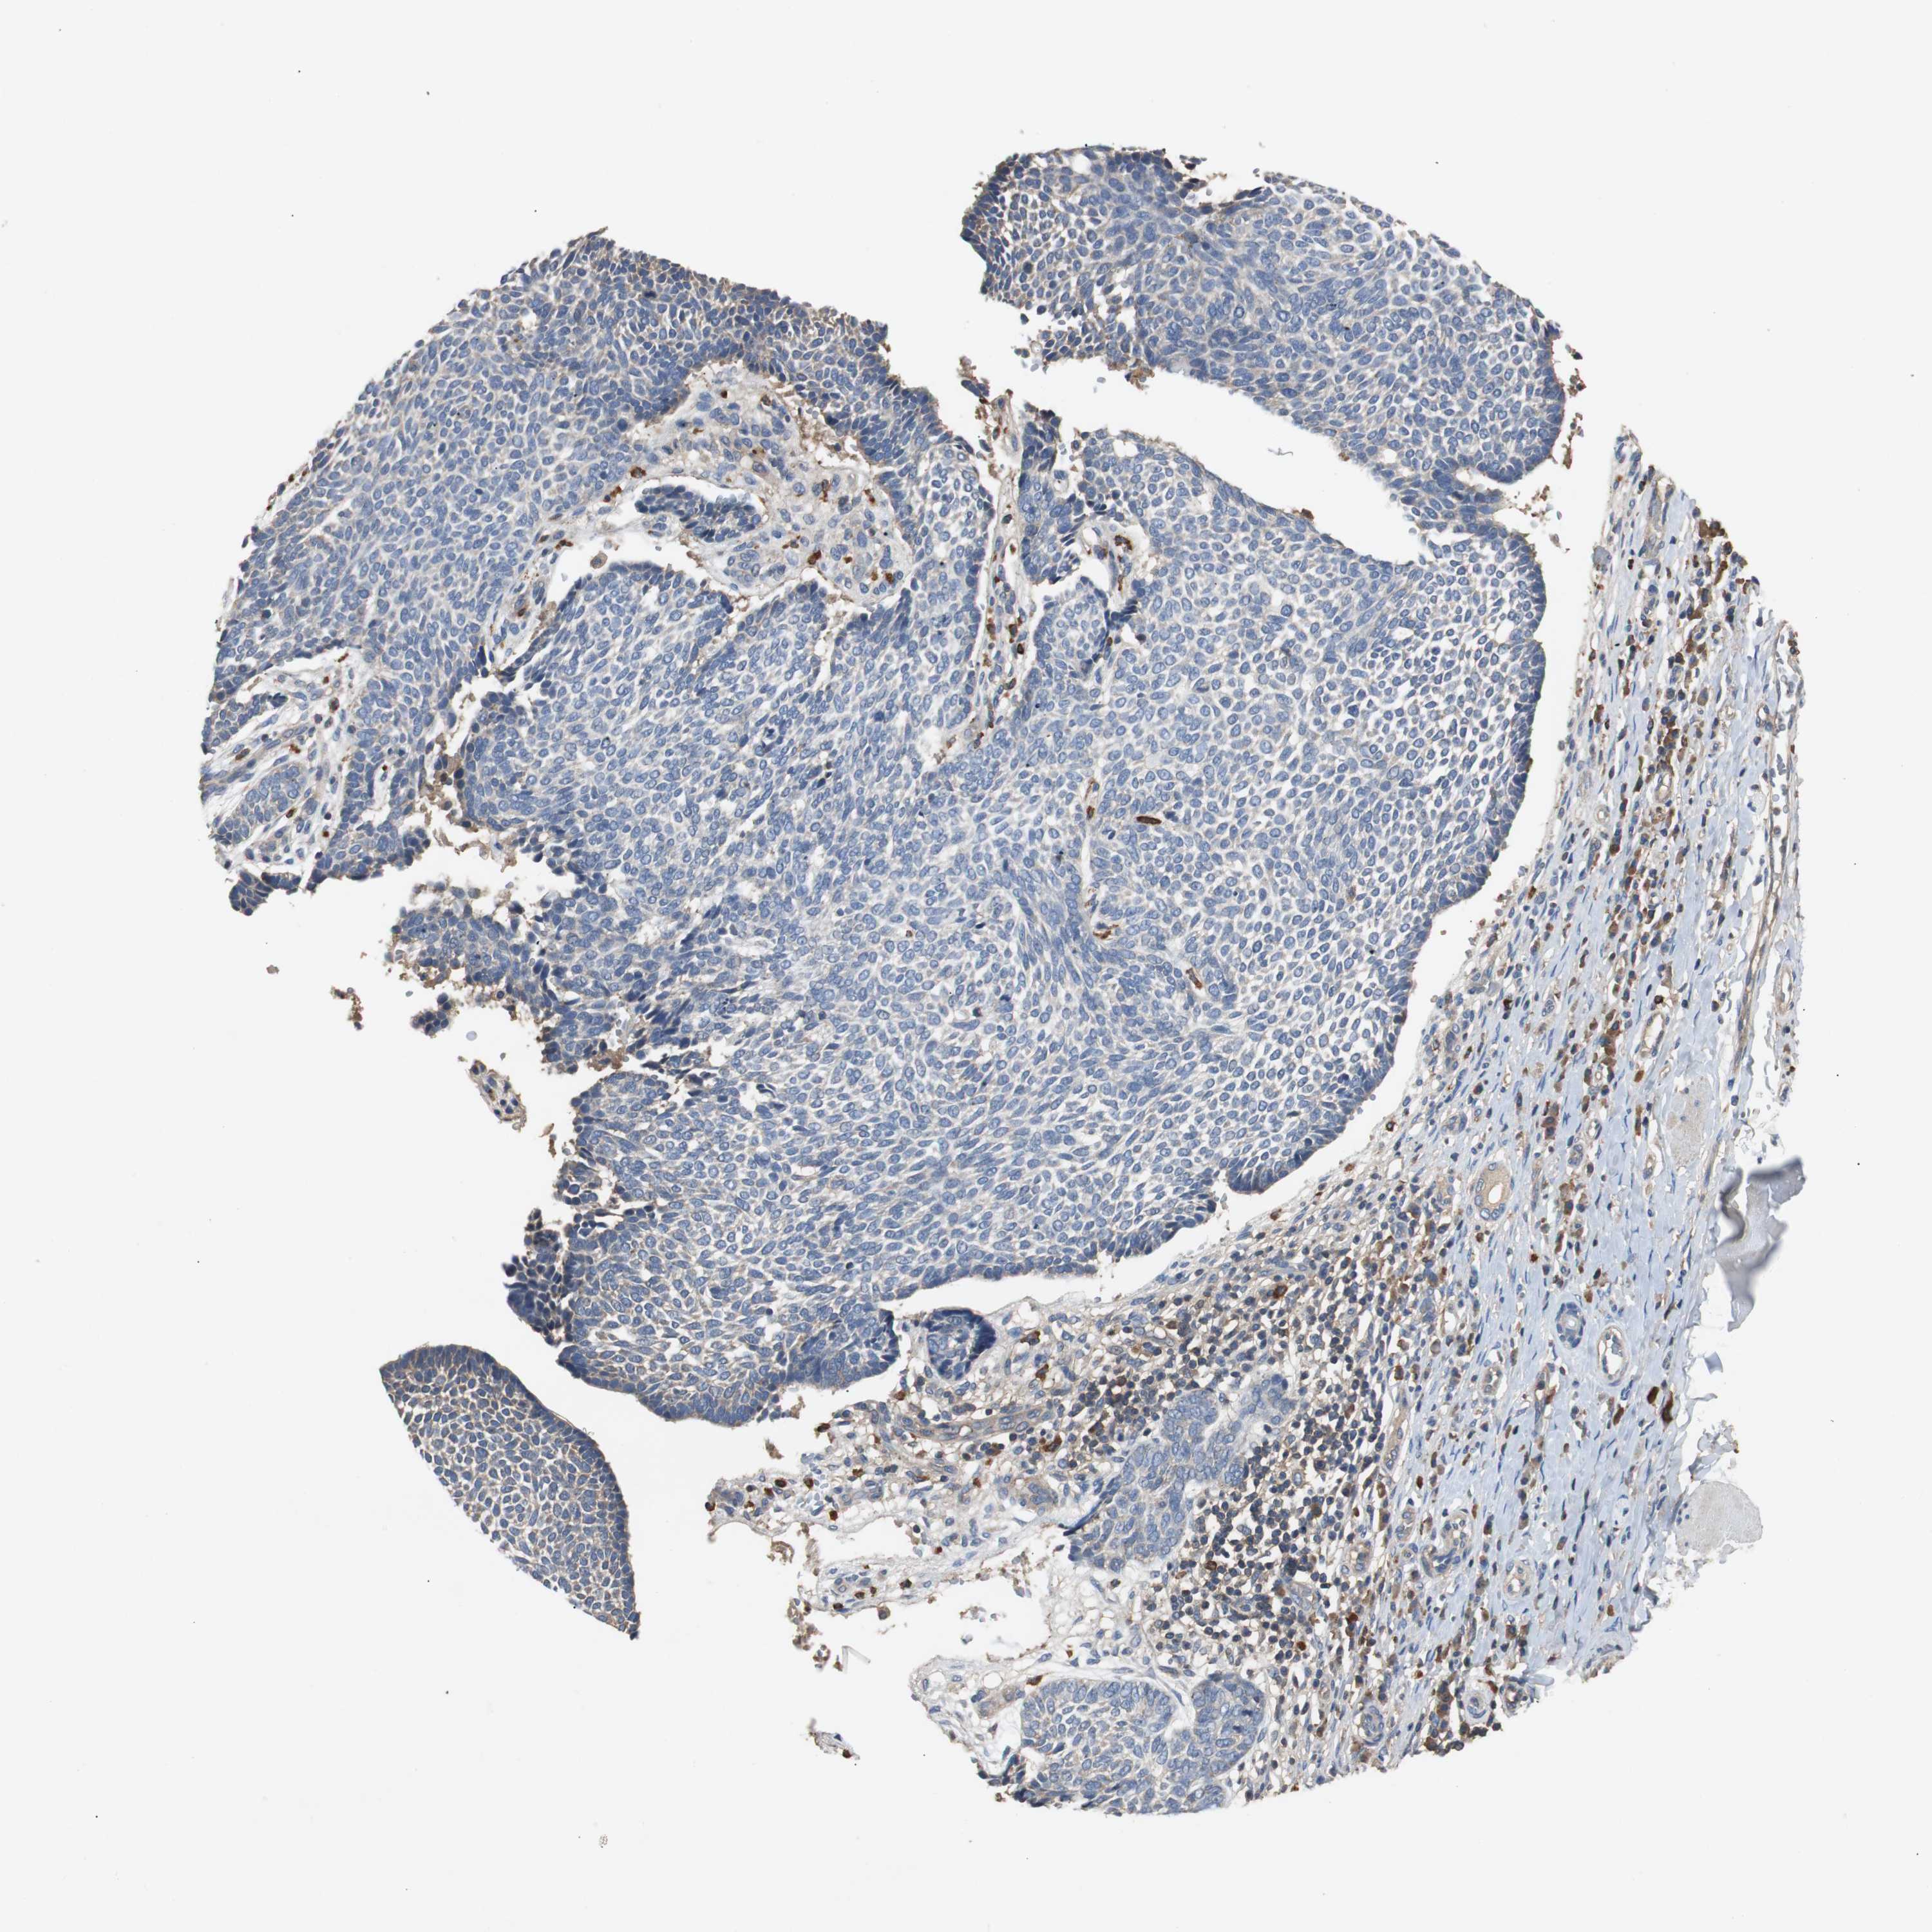

SKIN CANCER - Protein expressioni

A mouse-over function shows sample information and annotation data. Click on an image to view it in a full screen mode. Samples can be filtered based on level of antibody staining by selecting one or several of the following categories: high, medium, low and not detected. The assay and annotation is described here.

Antibody stainingi

Antibody staining in the annotated cell types in the current human tissue is reported as not detected, low, medium, or high, based on conventional immunohistochemistry profiling in selected tissues. This score is based on the combination of the staining intensity and fraction of stained cells.

Each image is clickable and will lead to virtual microscopy that enables deeper exploration of all samples and also displays staining intensity scores, fraction scores and subcellular localization as well as patient and tissue information for each sample.

Antibody CAB026150

Squamous cell carcinoma, NOS

Basal cell carcinoma